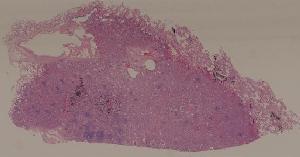

57.肺癌